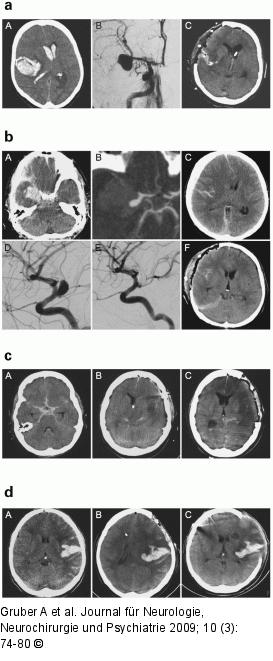

Abbildung 1a-d: Aneurysmatische Subarachnoidalblutung a: Entlastungskraniektomie zeitgleich mit Aneurysmachirurgie: In einem Drittel der Fälle wurden Patienten mit aneurysmatischer Subarachnoidalblutung und gleichzeitig bestehenden raumfordernden intrazerebralen oder subduralen Hämatomen durch Aneurysmaklippung, Hämatomentleerung und gleichzeitige großflächige osteoklastische Entlastungskraniektomie behandelt. – Management von intrazerebraler Massenblutung rechts temporal (A) nach Ruptur eines rechtsseitigen Mediabifurkationsaneurysmas (B). Die initiale Trepanation wird bereits als ausgedehnte Entlastungskraniektomie angelegt, durch Hämatomentleerung sowie knöcherne und durale Dekompression ist eine Rückbildung von Massenverschiebung und Hirnstammkompression möglich (C). Die akute Entlastung raumfordernder Blutungen nach Aneurysmaruptur ist an allen neurochirurgischen Fachabteilungen gängige Praxis und kann bei zeitgerechter Operation vergleichsweise günstige neurologische Langzeitverläufe ermöglichen. b: Entlastungskraniektomie nach endovaskulärer Aneurysmatherapie: In unserer Population fanden sich 2 wesentliche Indikationen zur Dekompressionsoperation nach initialer endovaskulärer Aneurysmatherapie. In einer Gruppe wurden unmittelbar nach Embolisation des Aneurysmas [101, 102] Entlastungskraniektomie und Blutungsentleerung durchgeführt. Dieser Behandlungsalgorithmus wurde in der rezenten Literatur wiederholt beschrieben [103] und wird naturgemäß kontroversiell diskutiert, da die Dekompressionsoperation durch die vorausgehende endovaskuläre Aneurysmatherapie verzögert wird [104–106]. In der anderen Gruppe fanden sich Patienten, welche im Rahmen des sequenziellen Hirndrucktherapiekonzeptes Tage nach Aneurysmatherapie therapierefraktäre Hirndruckkrisen entwickelten und kraniektomiert wurden. – Behandlung von akutem Subduralhämatom rechts parietal (A) und intrazerebraler Blutung rechts temporomesial (B) nach Ruptur eines Aneurysmas am Abgang der Arteria communicans posterior (C, D). Nach akuter Versorgung des Aneurysmas durch Coil-Embolisation (E) wird eine dekompressive Entlastungskraniektomie durchgeführt (F). c: Verzögerte Entlastungskraniektomie: Dem in Tabelle 1 dargestellten Therapiekonzept folgend wurde nach initialer osteoplastischer Kraniotomie und Aneurysmaklippung bei Eskalation der konservativen Hirndrucktherapie im weiteren intensivmedizinischen Krankheitsverlauf die Indikation zur Entlastungskraniektomie gestellt. Die Ursachen der Hirndrucksteigerungen waren sowohl Resthämatome als auch diffuse Hirnschwellungen und ischämische Territorialinfarkte. – Dekompressive Entlastungskraniektomie im Rahmen des sequenziellen Hirndrucktherapiekonzepts zur Behandlung konservativ therapierefraktärer Hirndruckkrisen. Nach initialer osteoplastischer Trepanation zur chirurgischen Aneurysmatherapie (A) wird bei zunehmender Hirndruckentgleisung nach Ausschöpfung von Basismaßnahmen und Standardtherapie sowie nach Ausschluss raumfordernder spasmusassoziierter Infarkte (B) die Indikation zur Entlastungskraniektomie gestellt (C). d: Rekraniektomie: In einer weiteren Subgruppe (A) wurde bereits im Zuge der initialen Aneurysmachirurgie eine osteoklastische Trepanation durchgeführt, deren suboptimale Größe und Form im weiteren Verlauf schwere Hirndruckkrisen nicht verhindern konnte. In diesen Fällen wurde in einem Zweiteingriff die ursprüngliche osteoklastische Trepanation (B) soweit technisch und anatomisch möglich erweitert, um eine maximale zerebrale Dekompression zu ermöglichen (C). Auch in dieser Gruppe waren die Ursachen der sekundären Hirndrucksteigerungen multifaktoriell und beinhalteten sowohl Resthämatome als auch Hirnödeme und ischämische Territorialinfarkte. |